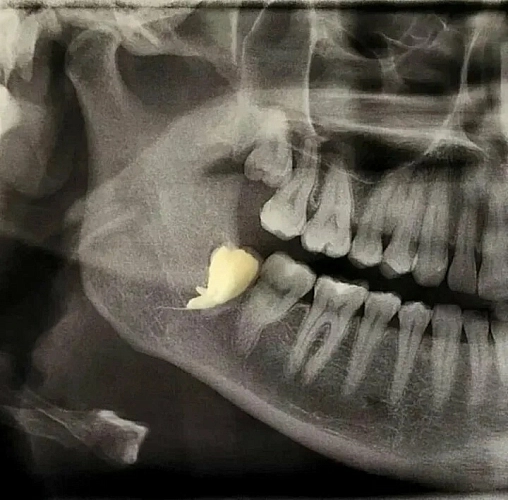

Восьмой зуб располагается в задней части челюсти и может вызывать проблемы, если у человека недостаточно места для его нормального прорезывания. В таких случаях восьмой зуб может расти под углом или даже горизонтально, оказывая давление на седьмой. Со временем это давление может привести к смещению седьмого зуба и нарушению прикуса, что создаёт дискомфорт при жевании.

Постоянное давление восьмого зуба на седьмой может привести к резорбции корня последнего. Это означает, что корень седьмого зуба может начать разрушаться под воздействием давления. Кроме того, воспаление десен вокруг восьмого зуба может вызвать отек и боль, что усугубляет ситуацию.